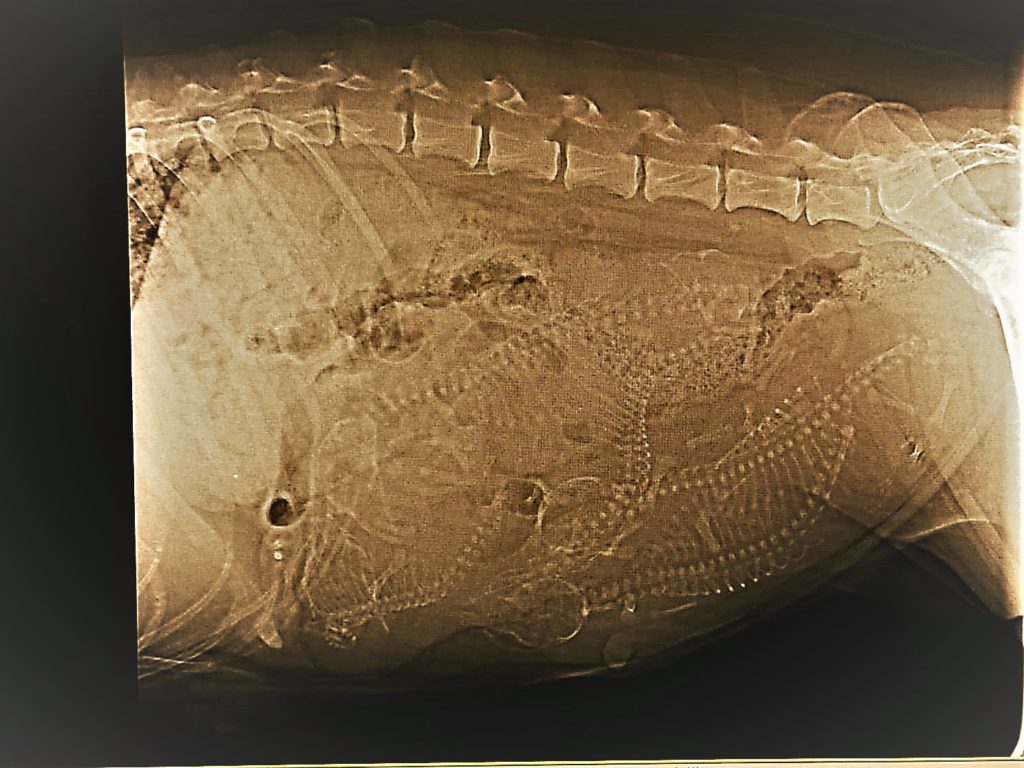

07.12.2018 Trächtigkeitsröntgen

Alajuela x Nvictus – 57. Tag der Trächtigkeit – na, wie viele Welpchen zählt ihr?